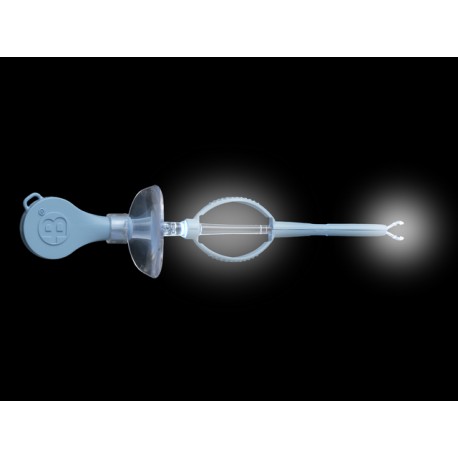

Kit Pince Lumineuse Bionix - Boite de 10 Kits

Kit Pince Lumineuse Bionix - Avec Lentille et Eclairage LED - Boite de 10 Kits

Pince lumineuse pour l'élimination des corps étrangers.

L'embout possède une amplitude de 90° pour faciliter l'élimination du cérumen du canal auditif.

Kit Pince Lumineuse Bionix - Avec Lentille et Eclairage LED - Boite de 10 Kits

Pince lumineuse pour l'élimination des corps étrangers.

L'embout possède une amplitude de 90° pour faciliter l'élimination du cérumen du canal auditif.